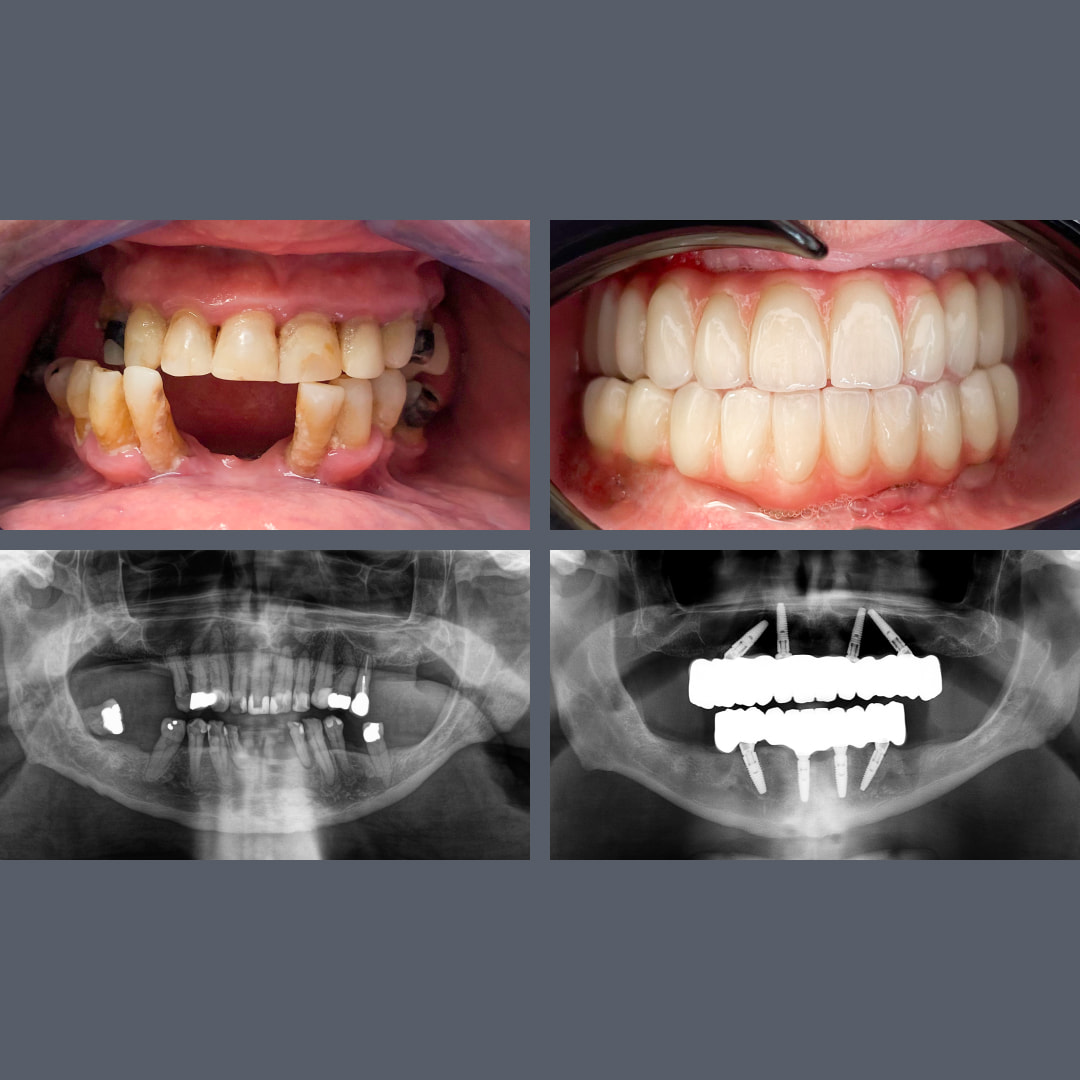

før og efter

All‑on‑4® – fast bro på 48 timer